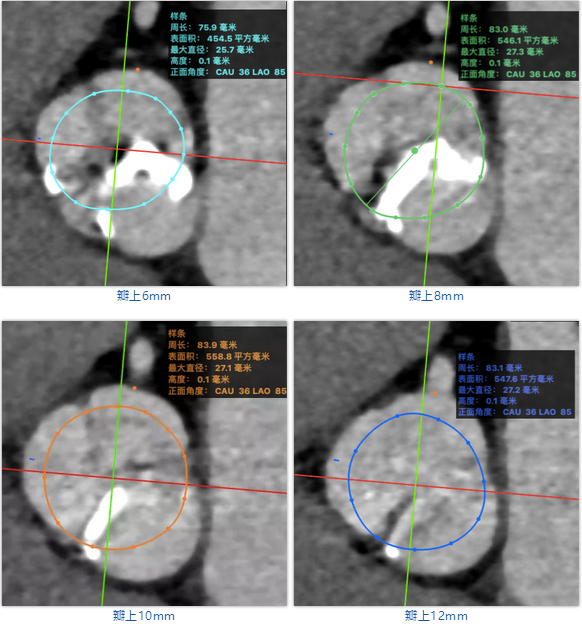

武汉协和董念国团队对该病例进行了缜密探讨,该病例为老年男性,主动脉瓣中重度狭窄,术前左室舒张功能减低。患者病例CT和心超数据显示瓣环瓣周长:90.2mm,瓣下4mm流出道周长:97.5mm,窦部空间相对小,单纯无冠瓣瓣叶钙化,三叶瓣。左冠风险较高,缜密分析瓣叶遮盖率>50%,术中可能存在阻挡风险,需要术中球囊扩张时仔细辨认,并准备冠脉保护策略。综合评估考虑右股动脉更适宜为主入路。经过团队严谨的评估及充分的讨论,决定先行25mm球囊预扩并进一步确认冠脉风险,并准备TAV29和TAV32规格的ProStyle预装式可回收TAVR系统。

术者采用患者右侧主入路,顺利完成导丝和猪尾跨瓣等准备工作。进Landerquist超硬导丝,采用25mm球囊进行预扩,仔细评估冠脉风险后,决定对冠脉采取保护措施。根据球囊扩张情况,术中决定使用金仕生物的ProStyle预装干瓣TAV32。打开包装后,很迅速的完成了瓣膜和系统植入前的准备。输送过程系统和瓣膜轻松过弓并顺利跨瓣;开始初步释放,然后快速起搏下释放,发现位置略高后进行回收,重新定位后最终成功完成释放。反复造影发现冠脉存在阻塞风险,武汉协和团队按照风险预案在左冠植入4.0*18mm支架进行保护。术后显示左右冠脉血液灌注通畅,术后超声测量峰值流速1.45m/s,峰值压差8mmHg,几乎无瓣周漏。入路闭合顺利,无心脏及血管并发症,手术成功。